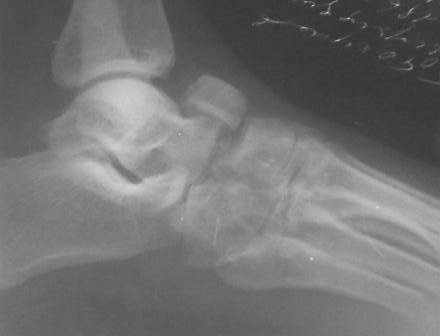

Уважаемый Абдурашид, с большой долей вероятности можно говорить о том, что в результате ДТП пациент плучил вывих в суставе Шопара с переломом одной из костей, скорее всего, действительно ладьевидной. Подтвердить это можно, попытавшись сделать более качественные ргр плюс снимки косым лучом для идентификации передних отделов таранной кости и таранно-ладьевидного сустава. Как я понимаю, выполнить КТ для данного пациента маловероятно. Тогда попробуйте воспользоваться таким старым, но в ряде случаев эффективным методом, как сравнительные Ргр здоровой конечности. Если Вы подтвердите д-з вывиха, а скорее да, по сохраняющемуся подвывиху, да иначе и сложно себе представить, как произошло такое смещение фрагмента, и, учитывая срок с момента травмы, Вам придётся выполнить артродез таранно-ладьевидного и, скорее всего, пяточно-кубовидного сочленений. С уважением, Волна

По данному случаю, оказалось 3 месяца назад было произведена Р-графия в райбольнице, но больной предпочел лечится у табиба. Присылаю первичные снимки.

Да, наш с Вами диагноз, Абдурашид, подтвердился. Я бы предпочёл артродез, фиксация- в самом простом варианте-винтами 3,5 или 4,5 . Отломок послужит аутотрансплантатом. Плюс внешняя иммобилизация. С уважением, Волна